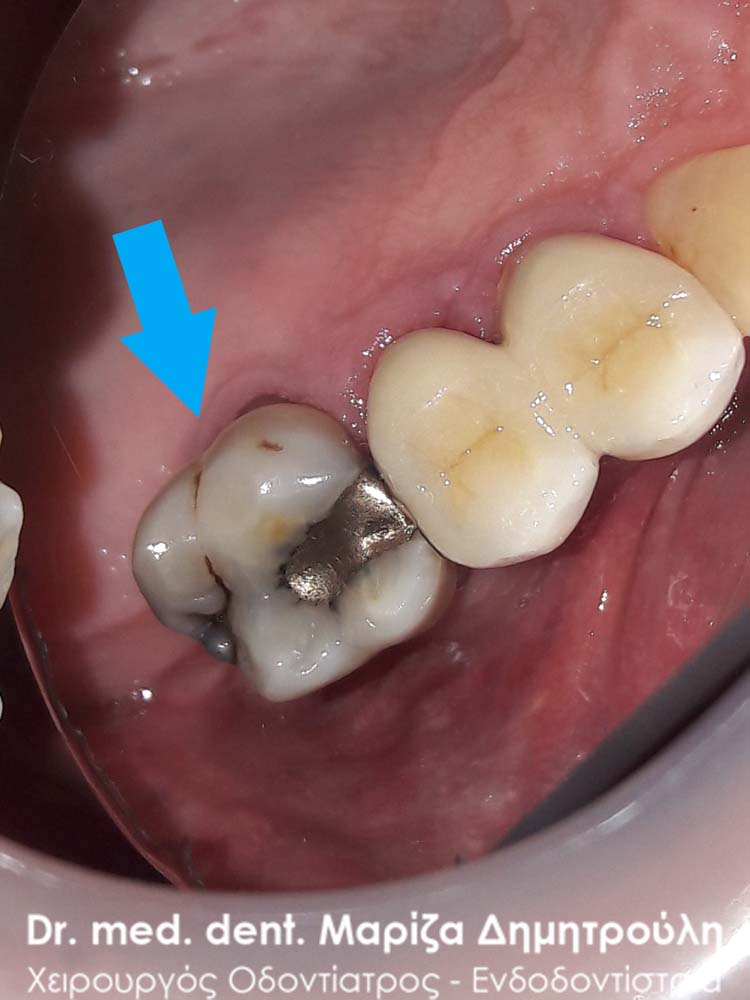

Η ασθενής επισκέφτηκε το ιατρείο καθώς ο πρώτος κάτω δεξιός γομφίος την πονούσε περιοδικά. Μετά την κλινική εξέταση διαπιστώθηκε ένα παλιό μεγάλο σφράγισμα αμαλγάματος, του οποίου τα όρια δεν είχαν επαφή με το δόντι και είχαν δημιουργηθεί κενά μεταξύ του μαύρου σφραγίσματος και οδοντικών τοιχωμάτων. Αποφασίστηκε η αντικατάσταση του παλιού σφραγίσματος με νέο λευκό σφράγισμα σύνθετης ρητίνης.

Η μεσαία φωτογραφία δείχνει την το έλλειμμα του δοντιού μετά την αφαίρεση του σφραγίσματος αμαλγάματος και των τερηδονισμένων οδοντικών ιστών. Στη δεξιά φωτογραφία φαίνεται η τελική αποκατάσταση του δοντιού.